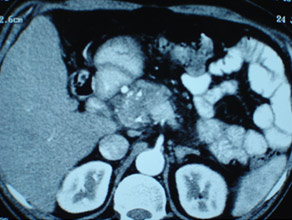

CT scan of chronic pancreatitis with large tumor, stones in the pancreatic duct